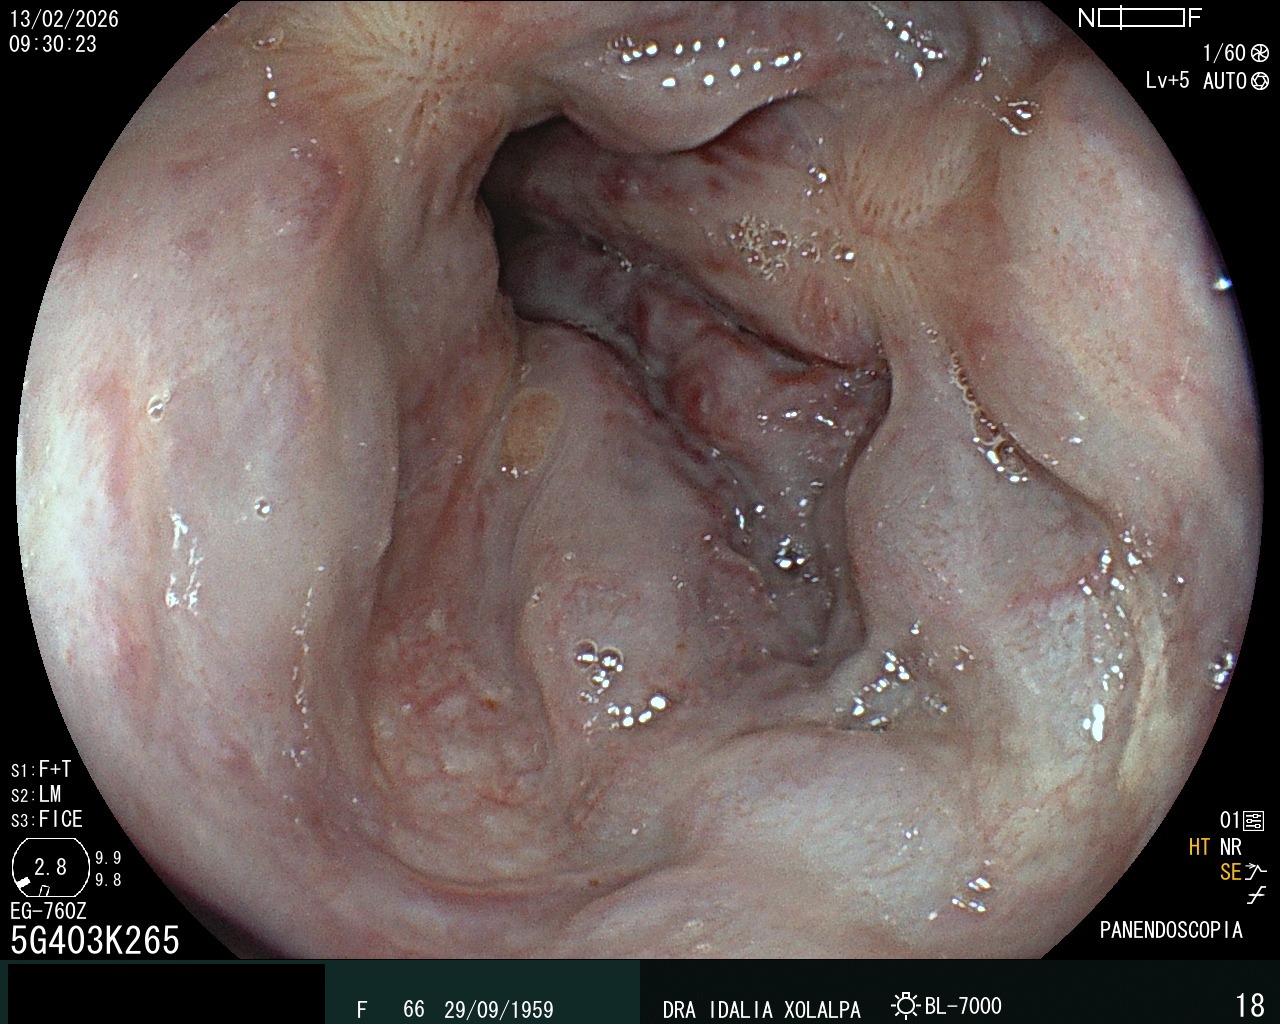

Gastritis Severa

Hallazgo de gastritis durante panendoscopia